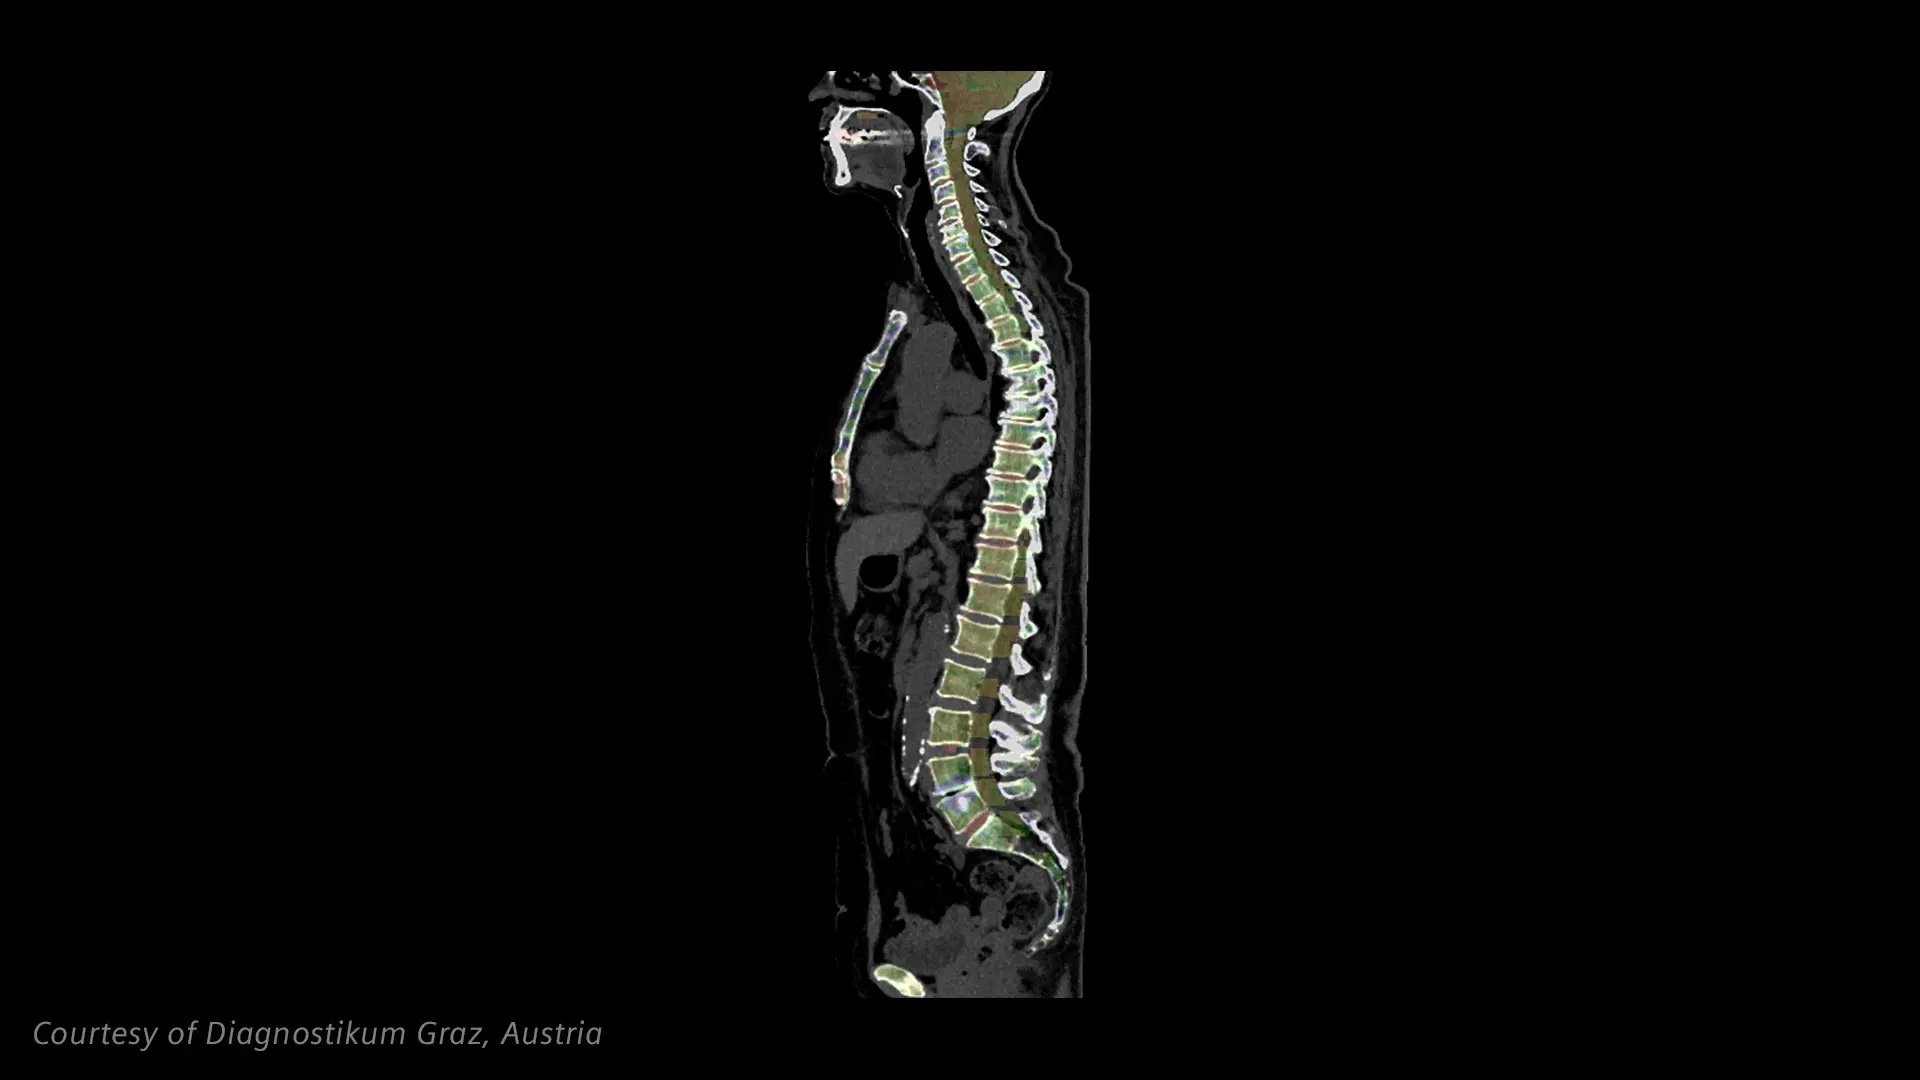

The ultra-high spatial resolution of NAEOTOM Alpha.Pro enables better diagnostic evaluation of coronary vessels than conventional CT with moderate radiation dose. The Dual Source temporal resolution provides unique insights into heart valves.

Quantum HD Cardiac at full temporal resolution of 66ms allows accurate assessment of patients with severe coronary calcifications. This potentially shifts patient pathways to more conservative treatment options.